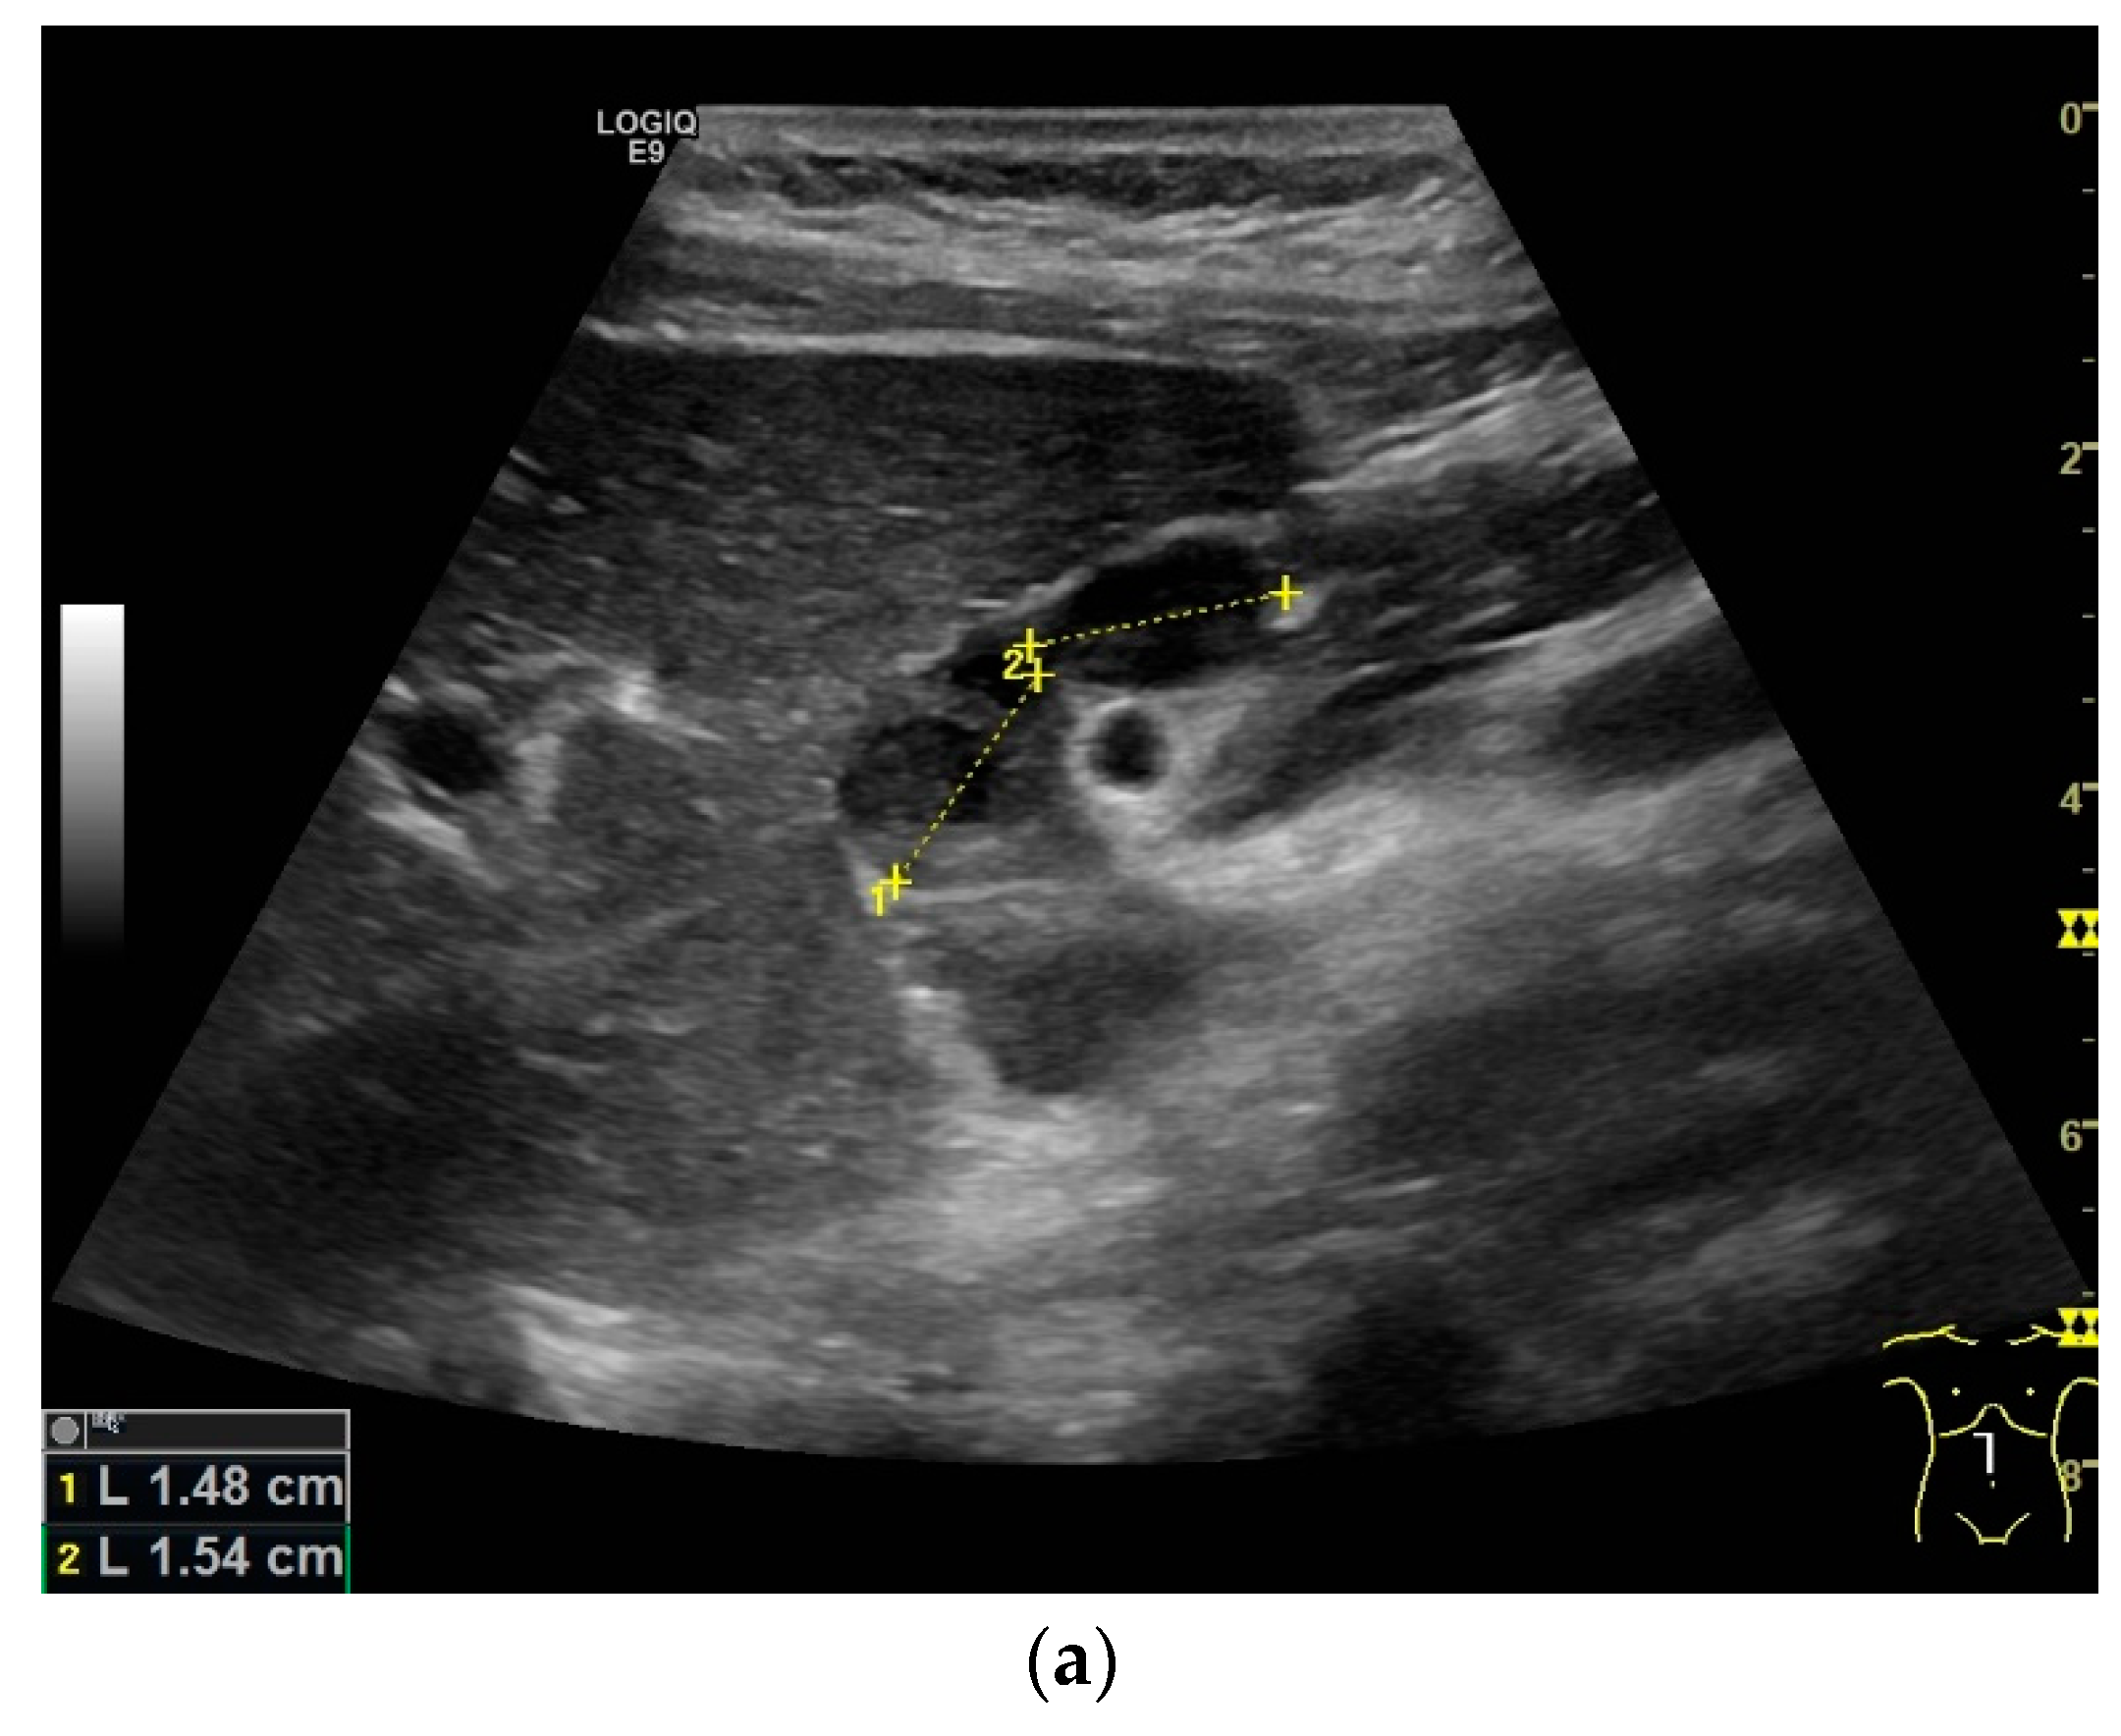

Mediastinal lymph nodes can be biopsied using EUS- or EBUS-guided FNA or FNB. Via paraoesophageal, paragastric, and paraduodenal access, histological specimens can be obtained from further lymph nodes using EUS-guided sampling [41,43,45,46,47,48,49,50] [Figure 2a–m]. The most important differential diagnoses are metastases of malignant tumors, non-Hodgkin’s and Hodgkin’s disease and other infections.

Figure 2.

A case of extrapulmonary tuberculosis: 33 y/o male from a country at high risk of tuberculosis. Thoracic pain and fever led to a suspicion of pericarditis. There was no pericardial effusion. There were no pulmonary infiltrations or pleural effusions in the chest CT, but there were enlarged mediastinal lymph nodes. Ultrasound and CT also showed subdiaphragmal enlarged lymph nodes and small nodular splenic changes. The diagnosis was confirmed using the transgastric EUS-guided biopsy (19 G Olympus) of the lymph nodes in the hepatic hilum. Enlarged lymph nodes in the hepatic hilum (a); adjacent to the pancreatic head (b); transabdominal ultrasound (TUS) using a linear transducer of 9 MHz. The hypoechoic central parts are conspicuous (a,b). Rounded lymph nodes are observed as being peripancreatic (c) and as being in close proximity to the gallbladder wall (d). The lymph nodes are visualized between the markers. In the EUS, paragastric lymph nodes are enlarged, rounded, very hypoechoic, with hypoechoic central parts, and forming conglomerates. A central vascular hilum cannot be delineated in the CDI (e). The hypoechoic central parts are softer during elastography (f). EUS also shows enlarged hypoechoic lymph nodes in the hepatic hilus, with hypoechoic central parts that lack a central vascular hilum (g). Elastographically, the lymph nodes are indifferent (h). The diagnosis is confirmed using EUS-guided biopsy (i) with evidence of granulomatous inflammation, caseous necrosis, detection of acid-fast rods, and Mycobacterium tuberculosis in the PCR. In the spleen, single hypoechoic lesions < 5 mm are visible during transabdominal ultrasound using a linear transducer of 9 MHz. Otherwise, fine-grained hypoechoic lesions can only be guessed at (j). With magnification using a 9 MHz transducer, multiple hypoechoic lesions < 3 mm can be delineated (k). These do not reveal any vessels in the Power Doppler (l). EUS confirms multiple hypoechoic splenic lesions, in line with splenic tuberculosis (m).